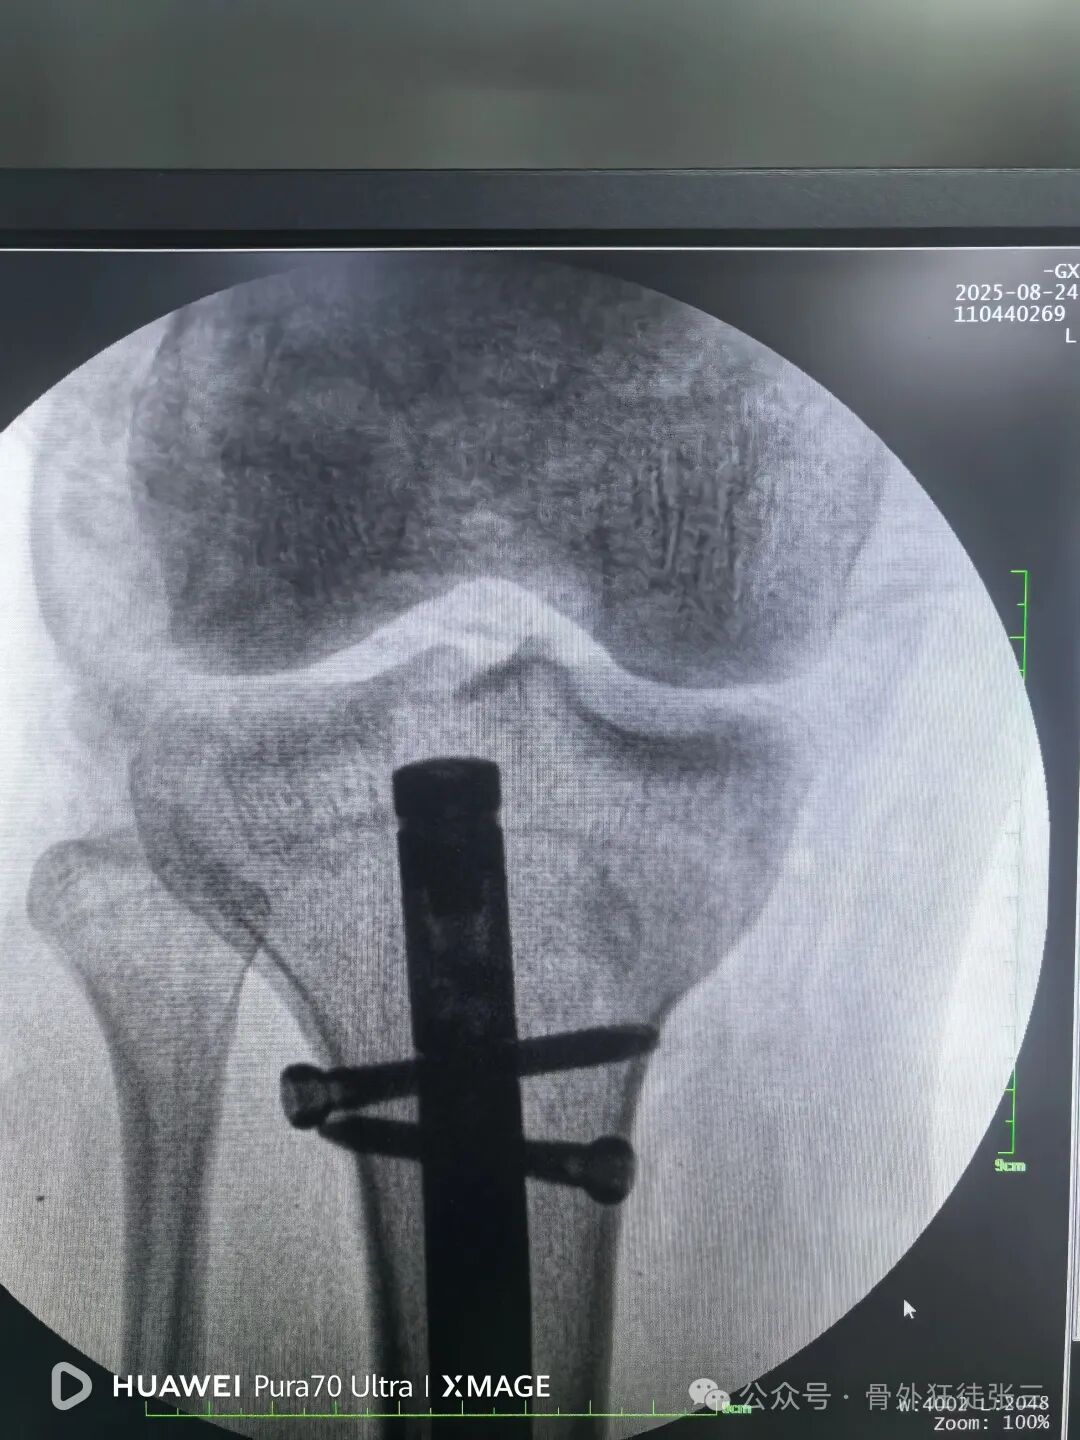

远端安装瞄准架

骨折间隙顺利缩小

锁近端两枚锁钉

侧位复位良好